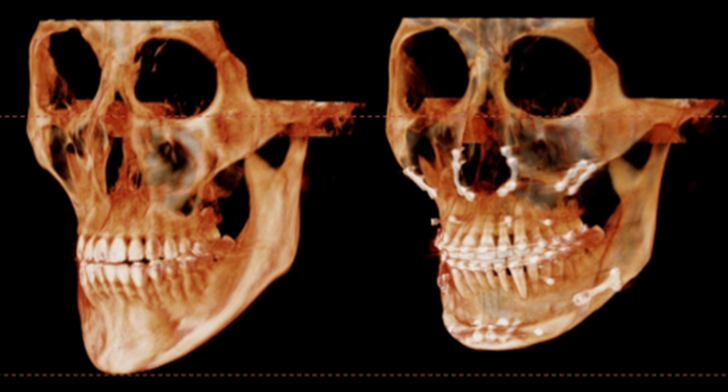

턱끝을 2단으로 절골하여 가운데 뼈를 제거하는 샌드위치 테크닉으로

턱끝의 길이를 5mm 줄이면서 앞으로 6mm 전진 시켰고,

단차가 생긴 뒷부분의 하악 하연을 매끄럽게 잘라낸 후 잘 다듬어서

앞턱 전체를 감싸면서 체부볼륨이 증가 될 수 있도록 이식하였습니다.

수술 3개월이 경과한 시점에 촬영한 CT입니다.

이식한 뼈는 자연스럽게 리모델링 되면서

거의 흡수 없이 잘 생착 된 상태로 회복하였습니다.